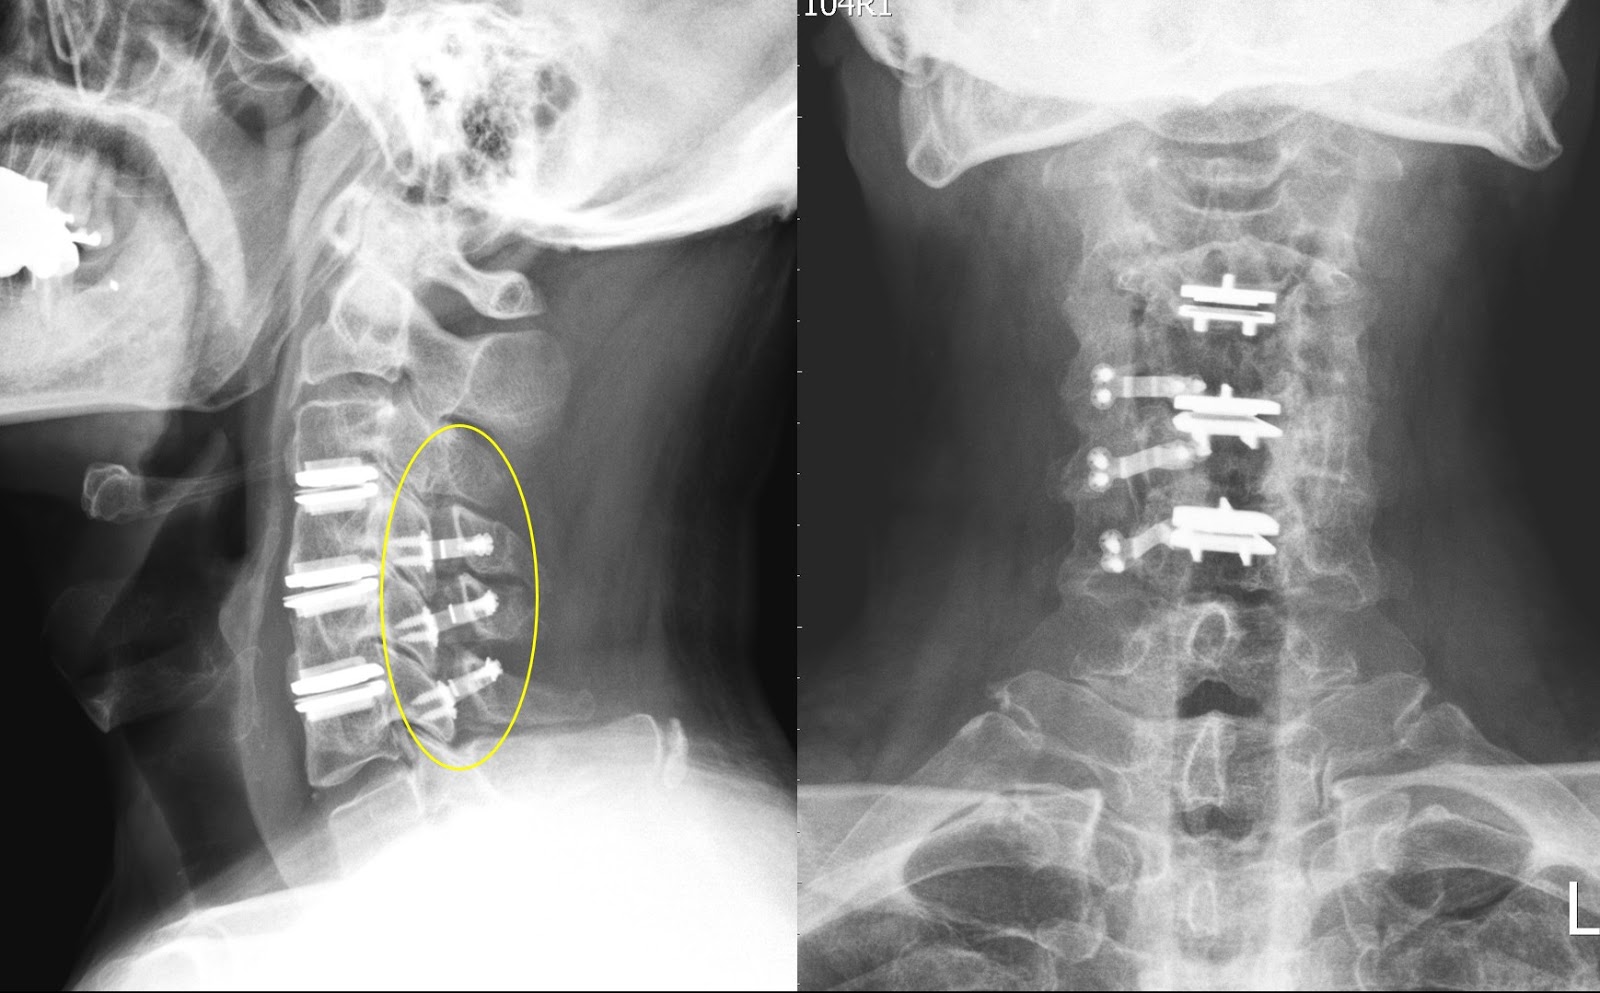

颈椎前路椎间盘切除及融合术是常见的颈椎手术,例如椎间盘突出、椎间盘退变性疾病及脊椎不稳定等。 椎间盘切除术是切除脊椎骨间的椎间盘及碎片,切除后,医生会以植骨填补之间的空隙。 此手术的目的是协助两块椎骨愈合在一起(称之为「融合」)。 在融合期间,为提高稳定性,医生可能会在脊椎骨上放入金属板(支架、镙丝及骨板)以巩固植骨。 治疗成效此手术可治疗由颈椎病所引致的症状,有助减低疼痛及预防进一步永久性神经损害,亦可改善颈部灵活性。 手术须在全身麻醉下进行。 颈椎开刀的位置因人而异,可能从左方或右方开刀。 在手术室可能会借助X光造影确定手术位置,由X-光导引确定病变位置,切除压在脊椎神经上的受损间盘及碎片。 减压后,可能需要进行颈椎融合术,把金属板固定在脊椎骨内以金属支架辅助支撑。